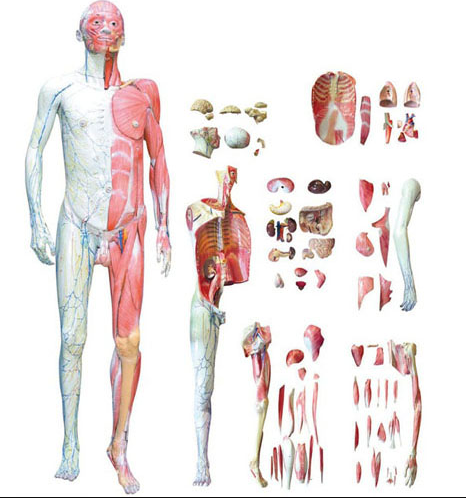

■ 尺寸:自然大,330×230×120mm;

■ 部件:1部件,置於底座上;

■ 功能:產品上至下頜骨下至胸骨(gǔ)柄(bǐng),示頸前部的淺層結構(gòu)。產品剝離淺筋(jīn)膜示部分舌骨上下肌群、甲狀腺、上腔靜脈在(zài)頸部(bù)的屬支,頸總動脈在(zài)頸部的分支。上腔靜脈在頸部的屬支有:頭臂幹頸內靜脈,甲脈腺上(shàng)中下靜(jìng)脈、頸外淺靜脈等(děng)。模型上頸總動(dòng)脈在頸(jǐng)部的分支有:甲狀腺上、下(xià)動脈, 頸內外動(dòng)脈、甲狀腺(xiàn)最下動脈等(děng),同時還示頸部的淺部神經;

■ 材質:進口環保PVC材料,進口環保油(yóu)漆。